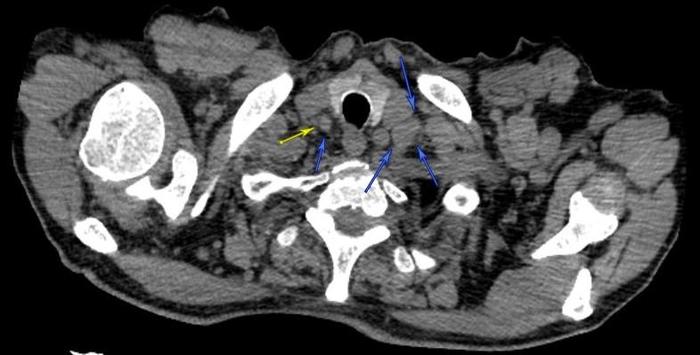

这个病人双侧锁骨上淋巴结肿大。如下图。

肿大淋巴结向下蔓延到盆腔里面的淋巴结肿大,向上蔓延到下颌下淋巴结肿大。

到处都是淋巴结肿大,最后颈部几次淋巴结穿刺未能确诊。